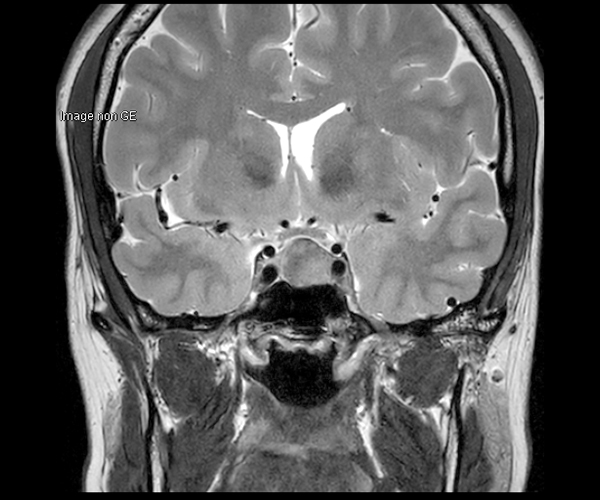

L’amélioration de la résolution spatiale s’applique à l’exploration morphologique des hippocampes dans le diagnostic de la maladie d’Alzheimer, à la détection de petites lésions de sclérose en plaques ou de métastases, à l’étude fine du cortex dans les épilepsies.

L’augmentation de l’effet de susceptibilité magnétique à plus haut champ permet d’améliorer la détection des hémorragies et est utilisé également dans l’imagerie de perfusion (tumeurs) et l’IRM fonctionnelle (BOLD). L’allongement du T1 à plus haut champ entraîne une meilleure saturation des tissus statiques et par conséquent une augmentation du contraste sang/tissus dans l’AngioIRM.